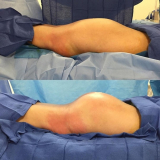

Lipoaspiração a Laser

Você merece a qualidade e comprometimento entregues pela equipe deste consultório médico e se neste momento está à procura de uma equipe que realize lipoaspiração a laser saiba que a FF Cirurgia Plástica disponibiliza de imediato este serviço para você!

Lipoaspiração a laser: atendimento eficiente e com qualidade que você sempre buscou!

Neste consultório médico você encontrará profissionais eficientes e com experiência de excelência. Usufrua de bom atendimento, através dos melhores preços do mercado e de assistência especializada sempre à sua disposição! Leve as suas dúvidas, converse com a equipe da FF Cirurgia Plástica. Contrate bons serviços e sinta-se mais seguro para cuidar da saúde.